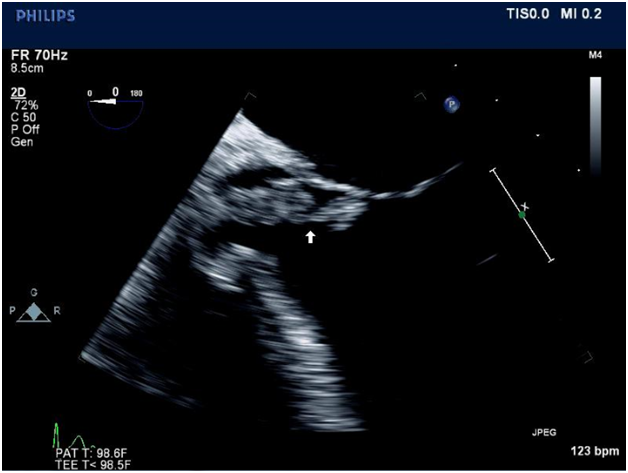

A 21-year-old female patient was admitted for further evaluation of severe acidosis and unresponsiveness. Trans-esophageal echocardiography demonstrated a large aortic valve vegetation (Figure 1) and severe aortic regurgitation. The patient was diagnosed with native aortic valve Staphylococcus aureus endocarditis and multiple cerebral intra parenchymal hemorrhages, bacterial meningitis, and Hepatitis C. Within hours of admission the patient developed severe heart failure, complete heart block, and pulmonary edema requiring mechanical ventilation and cardiopulmonary resuscitation. She was immediately taken to the operating room. Intra-operative trans-esophageal echocardiography revealed a sinus defect of the non-coronary sinus of Valsalva, a rupture of the sinus of Valsalva abscess into the right atrium with fistula formation and a new large vegetation at the tricuspid valve (Figure 2). Emergency surgery was carried out through median sternotomy with total cardiopulmonary bypass and venous drainage of the snared superior and inferior vena cava. The heart was arrested with hypothermic crystalloid cardioplegia, which was infused directly into the right and left coronary artery. Destroyed intra- and peri-annular areas from the atrial side and aortic area of the non-coronary sinus were closed with glutaraldehyde pre-prepared autologous pericardial patches. After debriding the abscess, repairing the fistula, and reconstructing the peri-annular defects, the annulus was re-examined and sized for replacement of a bio prosthetic artificial aortic valve. Twelve pledgeted 2-0 Tevdek sub-annular mattress sutures soaked in Linezolid were passed through the area reconstructed by pericardial patch and aortic annulus and through the sewing ring of a 19mm tissue aortic valve bioprosthesis. A diamond-shaped pericardial patch was placed in a supra valvular position near the superior vena cava, which assisted in a tension-free closure of the near circumferential aortotomy. Mean effective orifice area ratio measured 1.02cm2/m2. A completion trans-esophageal echocardiography revealed a functioning and competent bioprosthetic aortic valve, no evidence of paravalvular leakage, correction of the aorto-right atrial fistula, and an overall well-preserved left and right ventricular function. Prior to discharge, a permanent pacemaker was implanted.

Figure 1 Trans-esophageal echocardiogram. Arrow points to aortic valve vegetations.